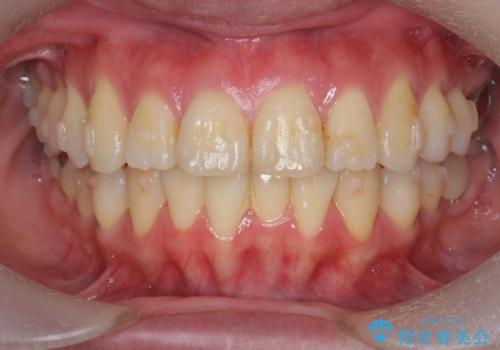

捻れた奥歯 突き出た前歯を治したい

- 出っ歯に見える前歯、捻れてしまった小臼歯の改善を求めて来院されました。

マウスピースでは改善の難しい小臼歯のねじれをまず部分ワイヤー矯正で改善し、その後マウスピース矯正で前歯の突出感を改善します。

時間はかかりましたが、捻れ、かみ合わせ、前歯の角度の改善が達成され満足いただくことができました。